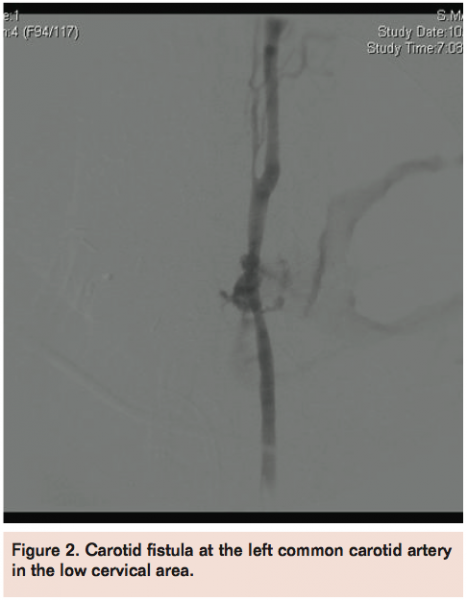

For the male patient, extravasation was visualized at the left common carotid artery at the thoracic inlet (Figure 1). For the female patient, carotid fistula was visualized at the left common carotid artery in the low cervical area (Figure 2).

In both cases, an iCast covered stent (Atrium Medical) (no cerebral protection used) was deployed across the common carotid at the area of extravasation. The hemorrhage was controlled. Completion left carotid angiography was performed and revealed widely patent left carotid stent with free flow of contrast noted intracranially (Figures 3 and 4). Intracranial views confirmed free flow of contrast without evidence of large-vessel intracranial obstruction. The procedure was then completed and the wire and sheath removed, followed by deployment of a 6 Fr Angio-Seal device (St. Jude Medical) achieving hemostasis. The patient was then taken to the recovery room.